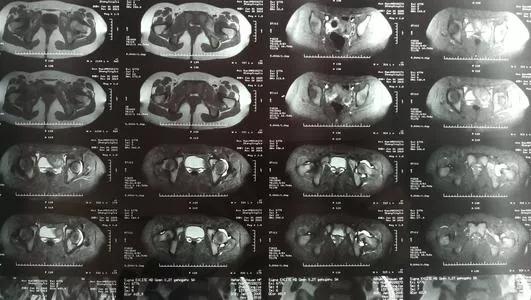

在膝关节存在症状的患者,应检查膝关节,除外其他疾病。这个疾病根据患儿的体征和症状基本可以诊断清楚,检查呢,可以做个磁共振看一看!一般表现是髋关节内可见有积液!B超检查也可以诊断!查血白细胞总数正常,或轻微升高。血沉正常或轻微升高,若血沉升高明显,超过20mm/h,结合体温升高超过37.5℃,白细胞计数增高等,提示感染性关节炎。